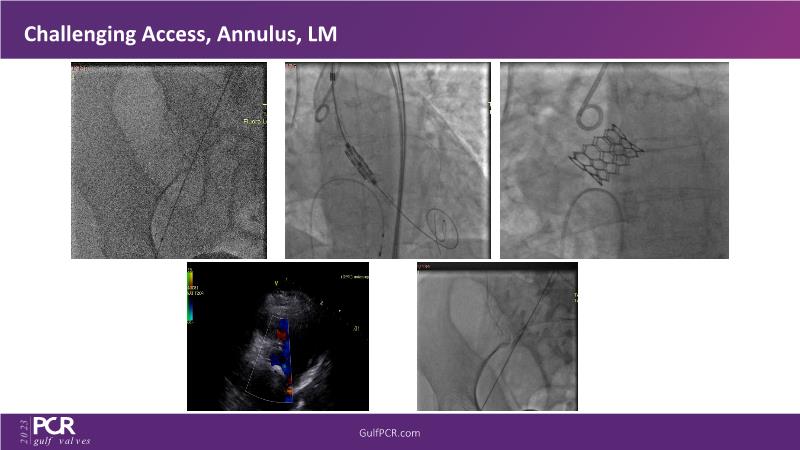

- To learn about the novel Myval next generation THV technology, its key features, procedural and clinical benefits and learn about the clinical data in a vast cohort of patient population

- To understand the CorAlign technique which enables predictable and precise commissural and coronary alignment thus preserving coronary access